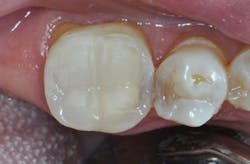

Traditional limitations were squarely in mind with the development of Activa BioActive Bulk Flow, which addresses these shortcomings. It self-levels easily, flows naturally, and exhibits elevated chroma and translucency matching. Independent testing demonstrates Activa BioActive Bulk Flow provides superior protection against microleakage,3 volume wear,4 and shrinkage stress,5 all at thresholds that meet or exceed existing standards for top-tier restorative materials.

The viscosity of Activa BioActive Bulk Flow is ideal for various clinical situations. For example, in cases requiring restoration of deep boxes and cavernous lesions, the material ensures proper treatment thanks to its flowability and dual-cure properties. With its unlimited depth of cure and no layering/capping requirement, dentists can be confident that the risk of voids is minimized.